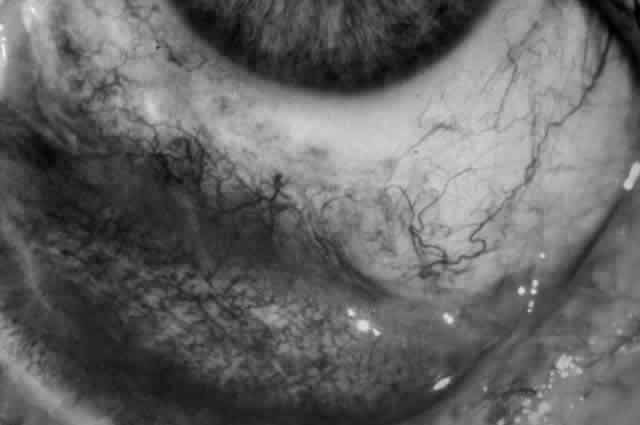

Clinically, the ocular disease in cicatricial pemphigoid (OCP) may present unilaterally in the form of a chronic, recurrent catarrhal conjunctivitis, but it eventually becomes bilateral. Subepithelial fibrosis is characteristic of stage 1 of OCP (Fig. 7). Stage 2 shows fornix foreshortening (Fig. 8), and symblepharon formation is the hallmark of stage 3 (Fig. 9). Stage 4, end-stage disease, is characterized by ankyloblepharon and surface keratinization (Fig. 10). Obstruction of the lacrimal ductules and meibomian gland ducts eventually produces an unstable tear film and progressive sicca syndrome, but it is to be emphasized that OCP is not a dry-eye syndrome until late in the disease course.20 Trichiasis and entropion occur because of the subepithelial fibrosis, with eventual keratopathy, corneal neovascularization, and corneal ulceration and scarring.20

Fig. 7. Stage 1 cicatricial pemphigoid, with cicatrizing conjunctivitis, and fine striae-type areas of subepithelial fibrosis, but without evidence of shrinkage of the conjunctiva.